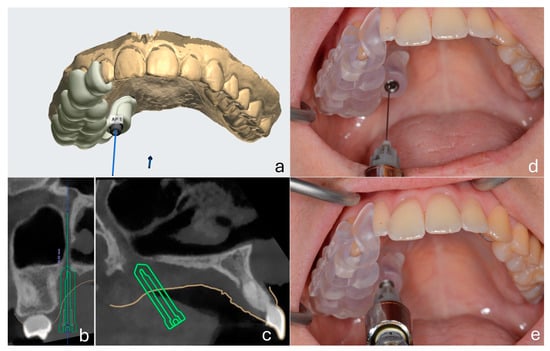

An Updated Digital Approach to Regional Anesthesia: A Pilot Study on Computer-Guided Maxillary Nerve Block via the Greater Palatine Canal

Objectives: Maxillary nerve block via the greater palatine canal (GPC) offers the potential for profound regional anesthesia of the maxilla but remains underutilized due to anatomical variability and technical complexity. The aim of this study was to explore the clinical feasibility, accuracy, and anesthetic effectiveness of a computer-guided approach by using CBCT-based surgical guides to access the pterygopalatine fossa via the GPC. Methods: Thirty-one patients underwent the procedure with patient-specific guides designed from cone-beam computerized tomography (CBCT) and intraoral scans. A 27G needle was directed through the guide to deliver 1.8 mL of 2% lidocaine with epinephrine 1:80.000. Pulpal anesthesia was assessed via electric pulp testing (EPT), and soft tissue anesthesia via pressure algometry at predefined oral and facial sites. Success was defined as absence of EPT response at maximum output and pressure pain threshold ≥ 700 g. To assess variations in anesthetic efficacy among multiple related groups, Cochran’s Q test and McNemar’s test were employed. Results: Successful needle placement was achieved in 30 out of 31 patients (96.7%) using the computer-guided approach, with a mean of 1.45 insertion attempts per case. Complete palatal soft tissue anesthesia was achieved in all subjects across the tested sites (100%). Pulpal anesthesia was most effective in posterior teeth, with success rates of 96.7% for first molars and 93.3% for first premolars, while the central incisor showed a reduced success rate of 50%. Transient visual disturbances occurred in three patients (10%), with no other adverse effects reported. Conclusions: These findings support the use of computer-guided GPC block as a method for achieving maxillary nerve anesthesia. Although anesthetic spread to anterior and buccal regions was limited, the technique demonstrated consistent effectiveness in the posterior maxilla, highlighting its potential utility in complex dental and surgical interventions requiring deep and long-lasting regional anesthesia. Full article